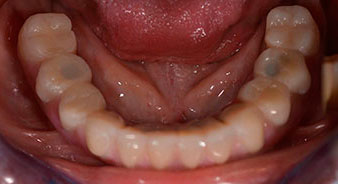

The 64-year-old patient presented with residual dentition of teeth 38, 33 and 43 and a clasp denture in the mandible (Fig. 1 and 2).

residual dentition

Fig. 2